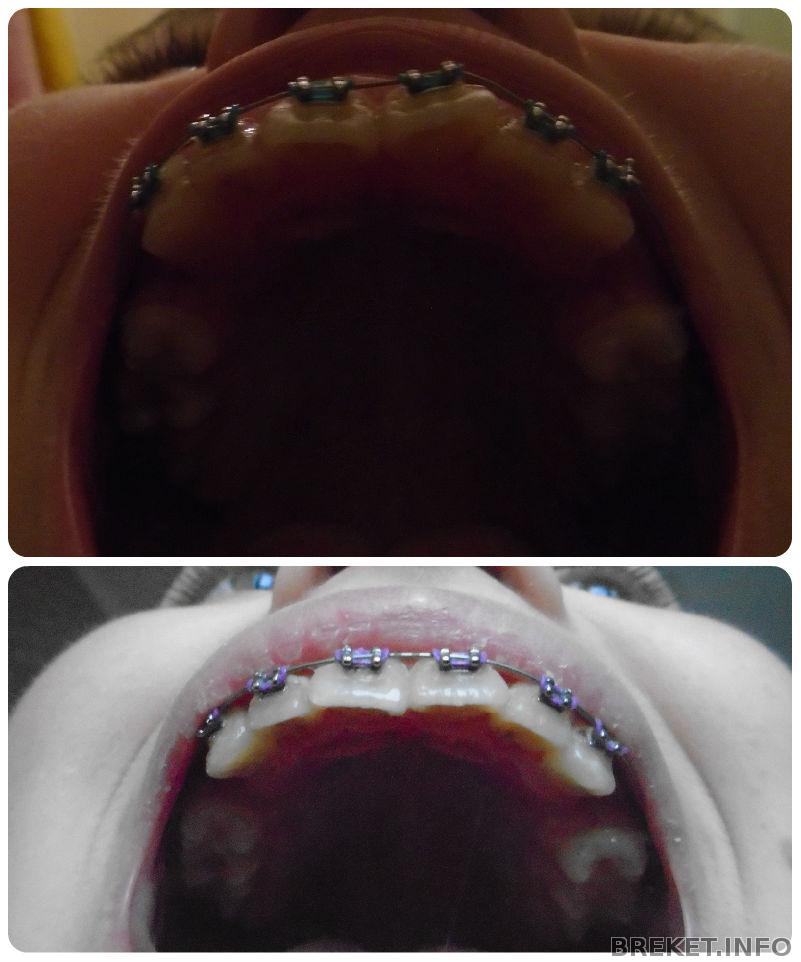

1.5 месяца

Вот уже и 1.5 месяца прошло.... Зубки двигаются медленно, но в верном направлении... Чему я конечно рада... Не по теме, но у меня очень сильно сохнут губы, ничего не помагает, может подскажите, чем вы пользовались)Ну а пока фотки для сравнения.... На первом коллаже разница 3 недели, на втором 2. А на последнем фото в один день только немного с разных ракурсов.